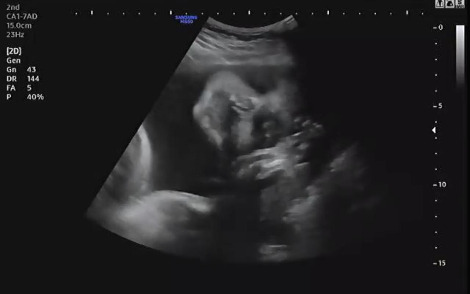

언제나처럼 진료시간에 맞춰 복부초음파로 태아의 상태를 확인했다. 시간이 지나감에 따라 내 품 안에 있던 아기는 초음파상으로 얼굴로 가득 차 보일만큼 성장하였다. 아이의 입이 꼬물거리며 움직이는 모습을 보며 설레는 마음으로 그동안 큰 이상은 없었는지 확인했다. 어느 때와 다름없이 햇님이는 자신이 건강하다는 것을 확인시켜주듯 양팔을 열심히 흔들며 엄마를 안정시켜줬다.